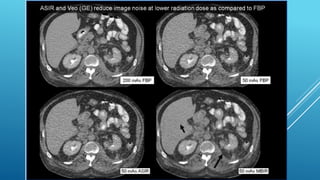

ADAPTIVE ITERATIVE STATISTICAL RECONSTRUCTION Thereare a large variety of algorithms used, but each starts with an assumed image, computes projections from the image, compares it with the original projection data, and updates the image on the basis of the difference between the calculated and the actual projections. These are called adaptive statistical iterative reconstruction algorithms. This new advanced reconstruction technique can reduce image noise, thereby improving image quality by improving low-contrast detectability. Compared with standard filtered back-projection methods, this technique has been shown to reduce the radiation dose to the patient by as much as 50%.

Most IRT resultsin changes in image appearance compared to FBP. Most IRT come in different strengths of noise reduction potential. Initial implementation IRT should generally start at low strength. IRT do not reduce dose by itself but rather allow user to reduce dose compared to FBP.